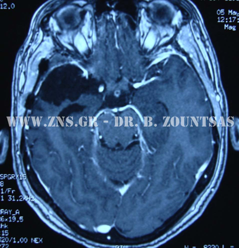

Ολική εξαίρεση μηνιγγιώματος πτέρυγας σφηνοειδούς

Ολική εξαίρεση μηνιγγιώματος λιθοειδούς αποκλίμματος